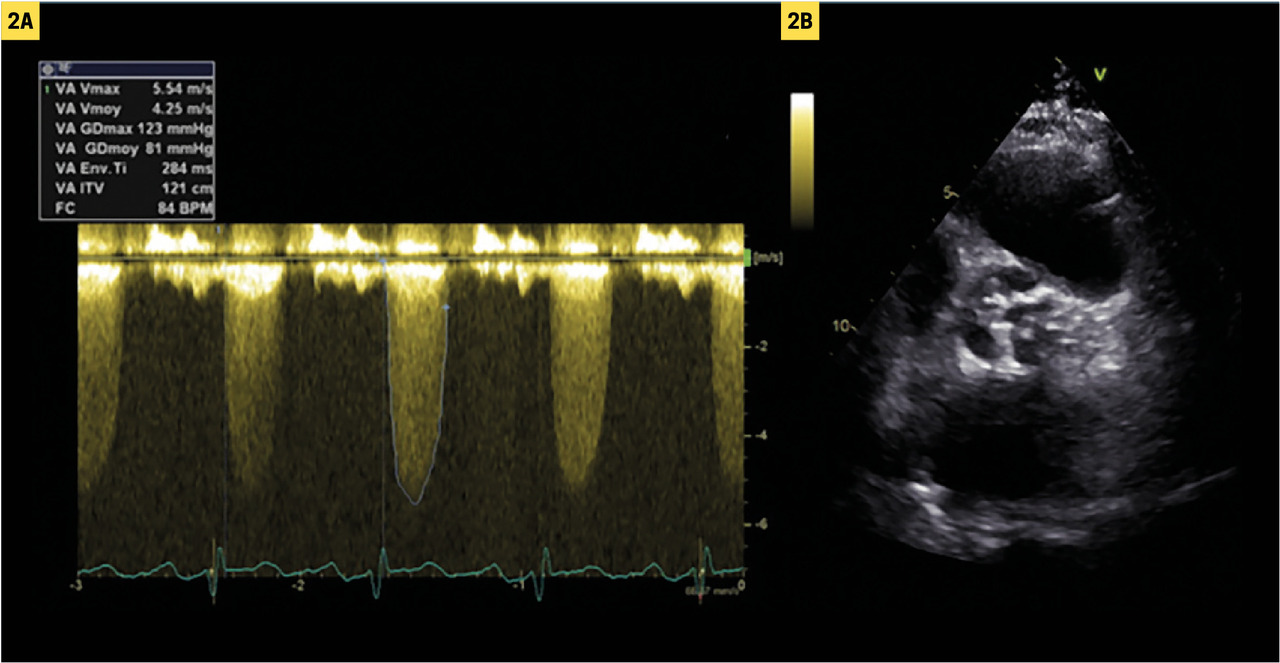

Pour simplifier, la sténose est considérée comme serrée si la vitesse maximale du flux transaortique en doppler continu (Vmax) est supérieure à 4 m/s ou si le gradient moyen de pression transaortique est supérieur à 40 mmHg (fig. 2).2 En l’absence de hausse pathologique du débit cardiaque, ces éléments suffisent en règle à faire le diagnostic de sténose serrée.